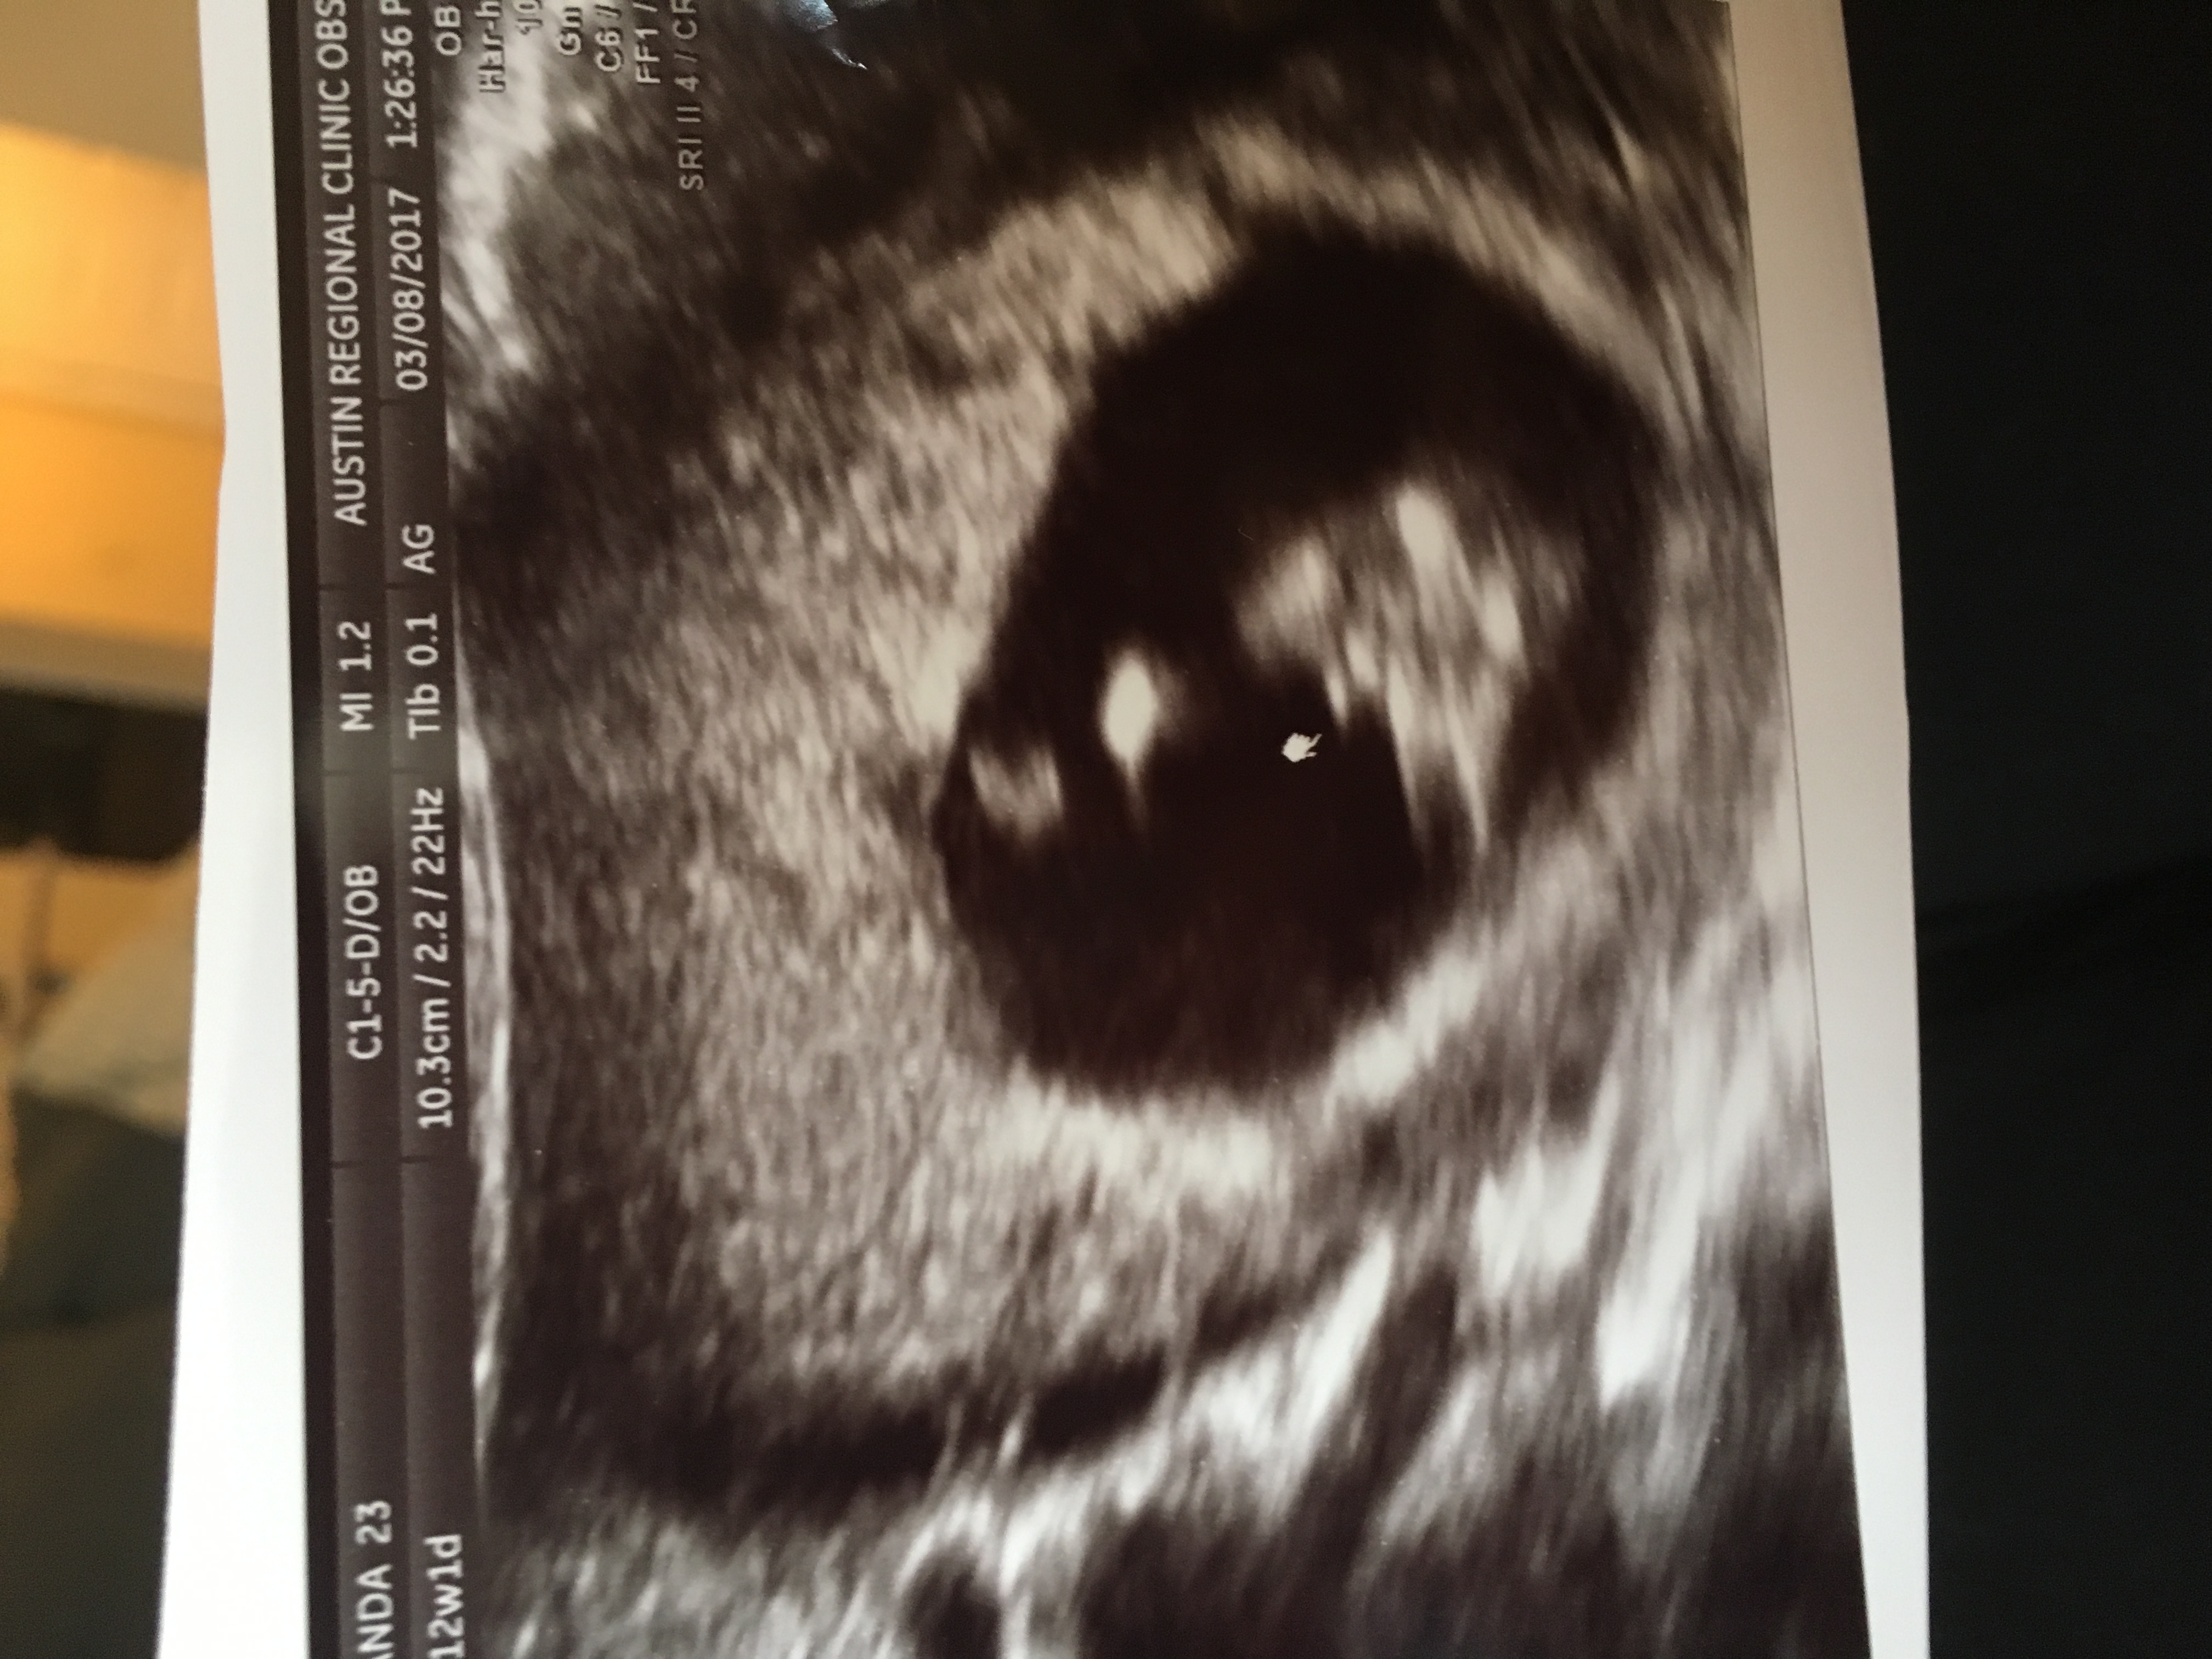

And here are my 12+1 pics

Attachment 36048